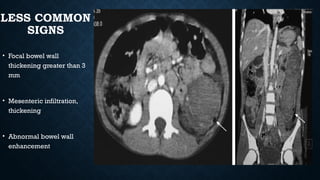

LESS COMMON

SIGNS

• Focal bowel wall

thickening greater than 3

mm

• Mesenteric infiltration,

thickening

• Abnormal bowel wall

enhancement